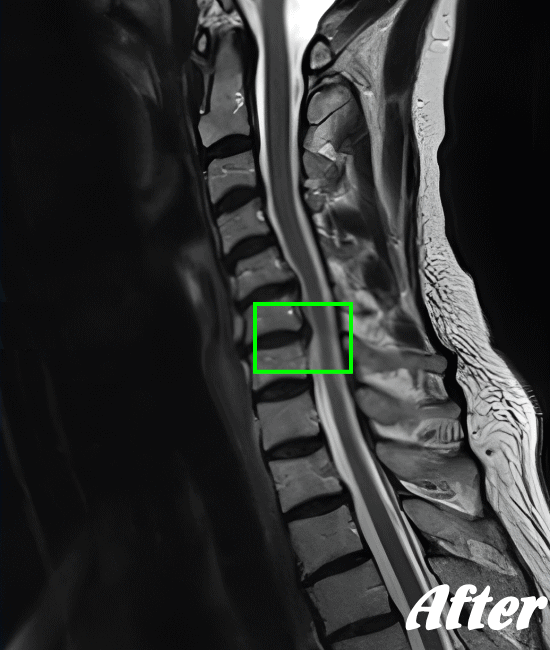

頚椎を斜め後方へ反らせると上肢に放散痛が現れたり、首の可動域、感覚異常があるかどうか…等々を確認した上で、レントゲンやCT、MRIなどによる画像検査を行います。

HALOカイロプラクティック☆平和島整体院では、骨盤から背骨全体を調整し、首(頚椎)の詰まりを一つ一つ広げ、肩甲骨の可動を柔軟にし、首周りの筋肉をゆるめることで、首の負担が解消され、痛みや痺れを改善していきます。

手術を要するヘルニアでない限り、多くの人は回復しています。